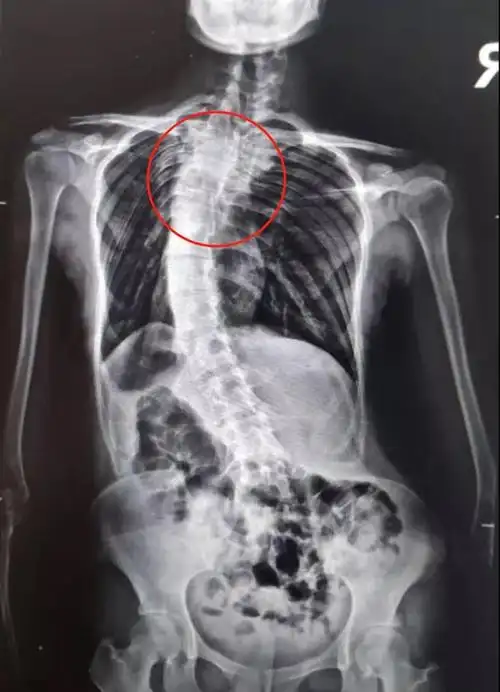

后路手术矫形治疗青少年特发性脊柱侧凸畸形(附图片资料) - 好大夫

所患疾病:脊柱侧弯 病情描述:女孩,14岁,刚刚检查x片子发现脊柱s形状